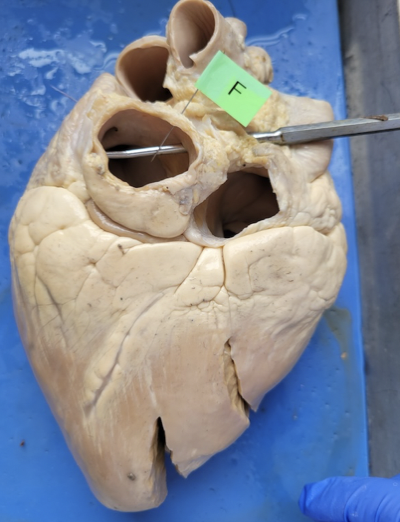

what is this

Aorta

what is this

the left ventricle

what is this

pulmonary artery

what is this

pulmonary vein